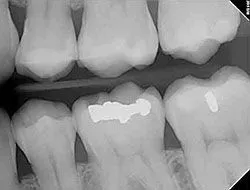

Digital X-rays

Using the most advanced dental technology possible is just as important as staying up-to-date on the latest treatment techniques. Because our practice is dedicated to providing you with the safest and most convenient treatment options available, we utilize advanced digital X-ray technology in our office.

Digital X-rays provide several advanced imaging options designed to save time, provide clearer dental photos, and expose patients to less radiation than traditional X-ray technology.